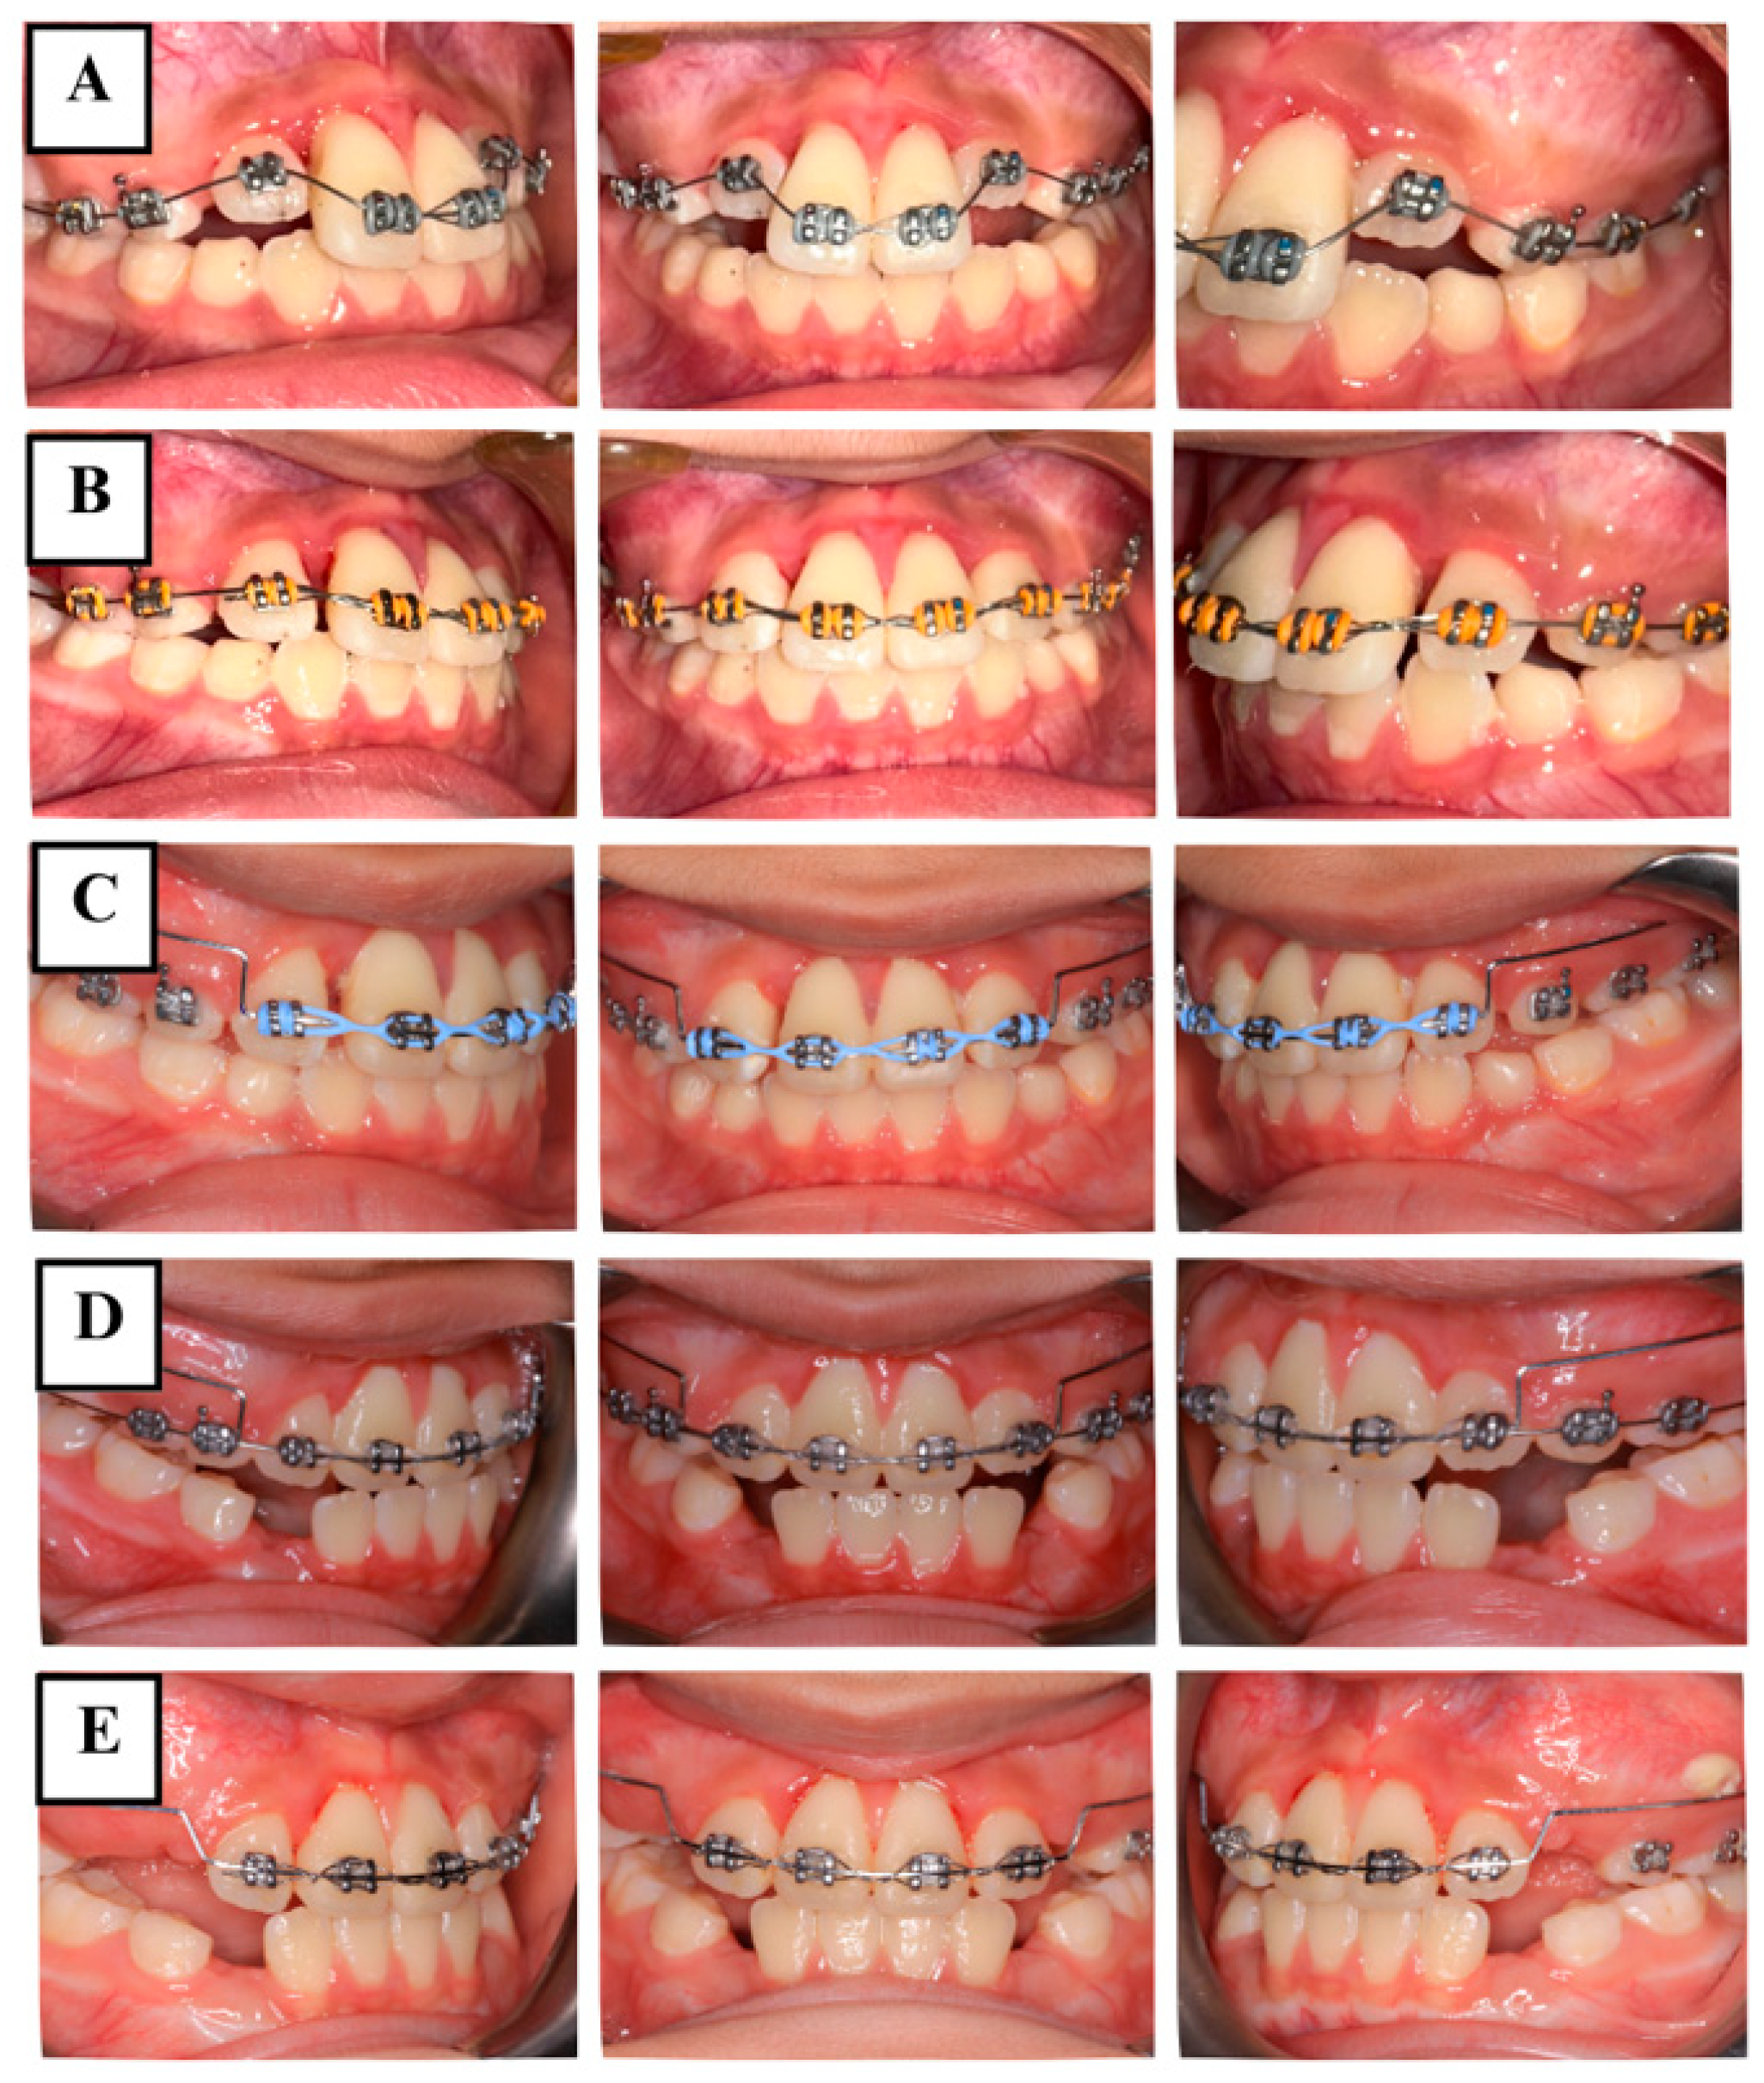

2.5.2. Phase 2: Orthodontic Management

2.5.3. Phase 3: Follow-Up